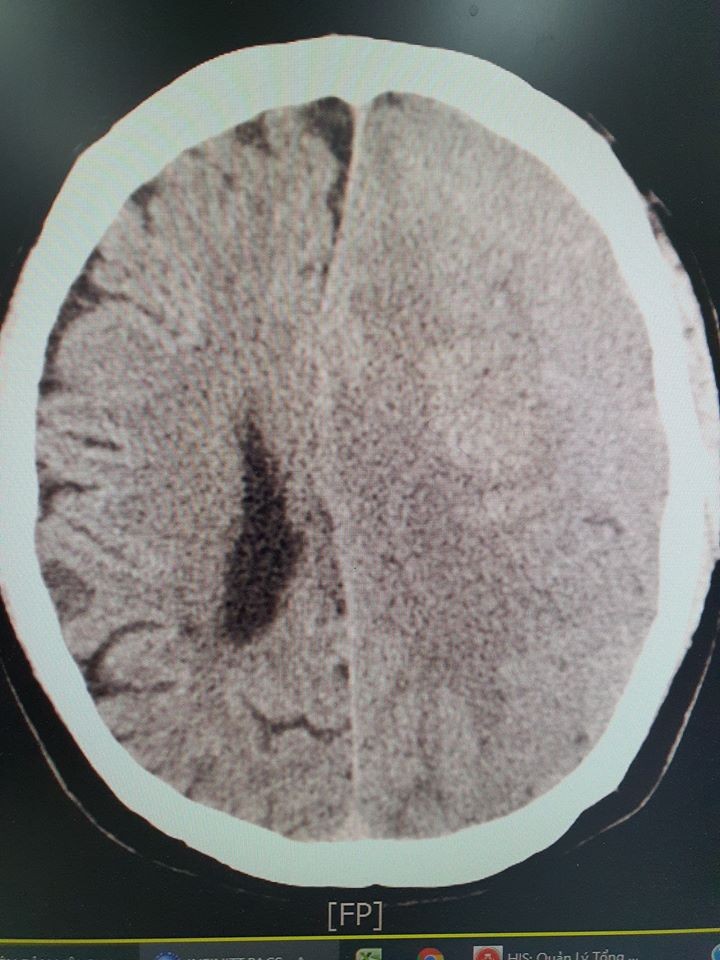

Khi tiếp nhận bệnh nhân, các bác sĩ đã nhanh chóng chỉ định chụp cắt lớp CT và phát hiện bệnh nhân bị xuất huyết não có cục máu tụ dưới màng cứng. Ngay lập tức, bệnh nhân được tiến hành xử lý lấy máu tụ và sức khoẻ ổn định sau 4 ngày can thiệp.

Chụp cắt lớp vi tính sọ não có hình ảnh chảy máu dưới màng cứng sau khi bệnh nhân dùng an cung ngưu.